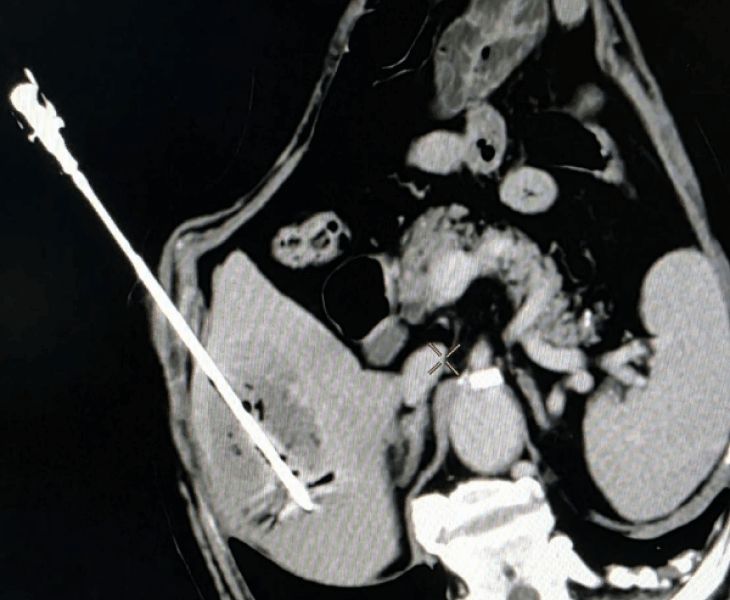

Kidney cancer treatment by Microwave Ablation method

- Procedures are performed under USG/CT guidance to precisely target the lesion while preserving as much normal kidney tissue as possible.

- Microwave ablation: delivers microwave energy to achieve rapid, predictable ablation zones, often suitable for selected renal tumours.